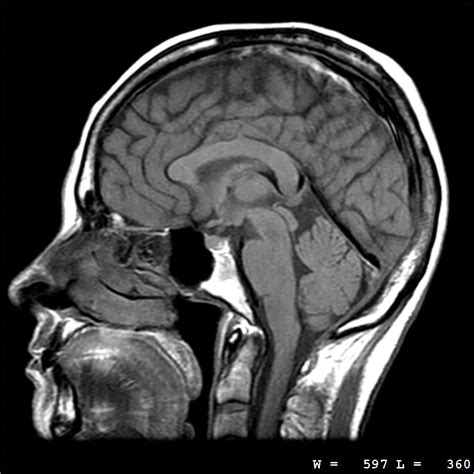

MRI scans are particularly good at visualizing soft tissues, such as the brain, spinal cord, muscles, ligaments, and tendons. This makes them invaluable for diagnosing a wide range of conditions, from sports injuries and arthritis to neurological disorders and cancer. The level of detail provided by an MRI scan allows doctors to see subtle abnormalities that might be missed by other imaging techniques. For instance, an MRI can clearly differentiate between different types of tissues in the brain, helping to diagnose conditions like multiple sclerosis or brain tumors with greater accuracy. In the musculoskeletal system, MRIs can reveal tears in ligaments, tendons, and cartilage, providing essential information for treatment planning. Moreover, MRI scans can also be used to assess the health of internal organs such as the heart, liver, kidneys, and pancreas. For example, cardiac MRI can evaluate heart function and detect abnormalities in the heart muscle, while abdominal MRI can identify tumors, cysts, or inflammation in the liver, kidneys, or pancreas. The versatility and high resolution of MRI scans make them an indispensable tool in modern medicine, aiding in the diagnosis, treatment planning, and monitoring of a vast array of medical conditions.

MRI scan images are incredibly versatile and can be used to visualize a wide range of conditions throughout the body. In the brain, MRIs can detect tumors, strokes, aneurysms, multiple sclerosis, and other neurological disorders. They’re also used to evaluate the spinal cord for injuries, tumors, and nerve compression. In the musculoskeletal system, MRIs are commonly used to diagnose torn ligaments, tendons, and cartilage, as well as arthritis and bone infections. They can also be used to assess the health of internal organs such as the heart, liver, kidneys, and pancreas, detecting tumors, cysts, inflammation, and other abnormalities. Furthermore, MRI scans can be used to guide biopsies and other minimally invasive procedures.